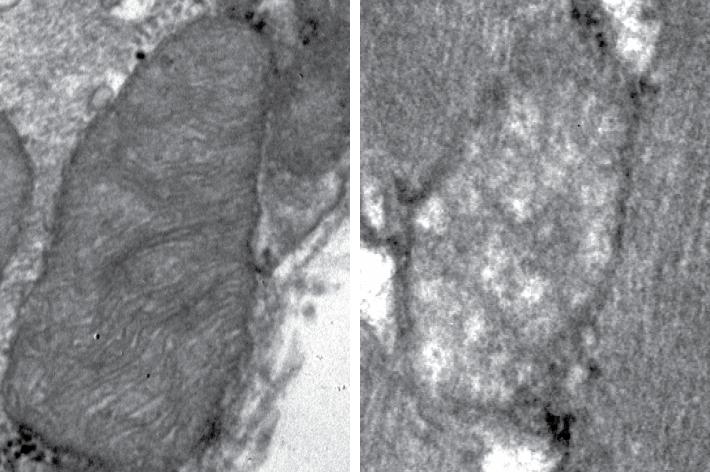

Mitofusin 2 is a mitochondrial protein involved in ensuring the correct function of mitochondria, and it has several activities related to autophagy, a crucial process for the removal of damaged mitochondria. The loss of Mitofusin 2 impedes the correct function of mitochondrial recycling and consequently damaged mitochondria accumulate in muscle cells.

Thanks to this study, the researchers have also identified and described an autophagy rescue system which kicks in regardless of Mitofusin 2 levels and allows cells to partially recover the mitochondrial recycling system in skeletal muscle. The scientists suggest that this could serve as an alternative metabolic mechanism used by Mitofusin to increase skeletal muscle autophagy and to maintain a healthier mitochondrial system.